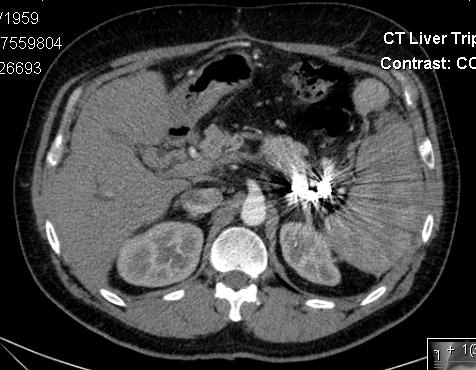

病例1: 已知原发性硬化性胆管炎(PSC),以前称开腹探查和开腹胆囊切除。现左侧腹痛,乳酸增高,碱剩余(Base Excess)-5,严重低血压。

脾门区动脉瘤

血管造影证实

微导管进入瘤囊

瘤囊内填塞微弹簧栓子和Onyx胶

术后